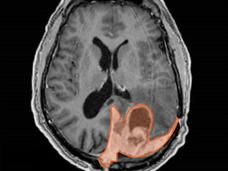

Una firma genética quizás ayude a personalizar el tratamiento del meningioma

En un estudio nuevo, se indicó que la actividad de 34 genes pronostica mejor la malignidad de los meningiomas. Esta firma de expresión genética ayuda a los oncólogos a seleccionar los mejores tratamientos para las personas con este tipo común de cáncer de encéfalo en comparación con los métodos vigentes.